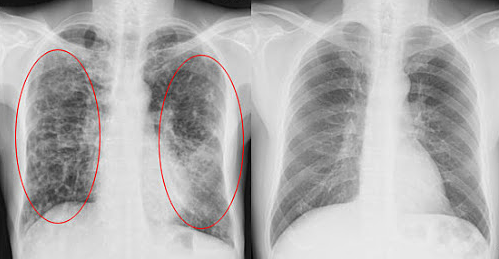

中国工程院院士钟南山就曾提出:“广州人的肺都是黑的,更何况北京!我最担心的还是雾霾会引发肿瘤!”

除了雾霾,生活中还有很多“伤肺”因素!比如吸烟、二手烟、油烟、粉笔灰、车间粉尘等,都会危害我们的呼吸道和肺!

英国著名yi学节目《BBC》就曾报导过:一位烟龄20年的老教师,患肺癌晚期去世。yi生做病理解剖时发现:“肺部已全部变黑,里面堆满了各种垃圾毐素!”